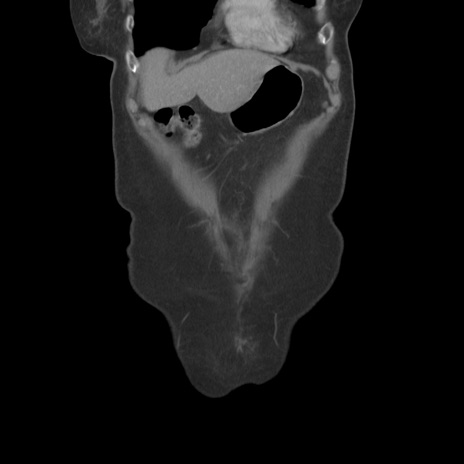

症例19(冠状断像)

【症例】80歳代女性

【主訴】下腹部痛

【現病歴】約8時間前より下腹部痛の出現あり、救急外来受診。

【既往歴】両側付属器切除

【身体所見】意識清明、下腹部正中に手術痕あり、その部位に一致して圧痛と反跳痛あり。腸蠕動音は亢進。

【データ】WBC 9300、CRP 0.15